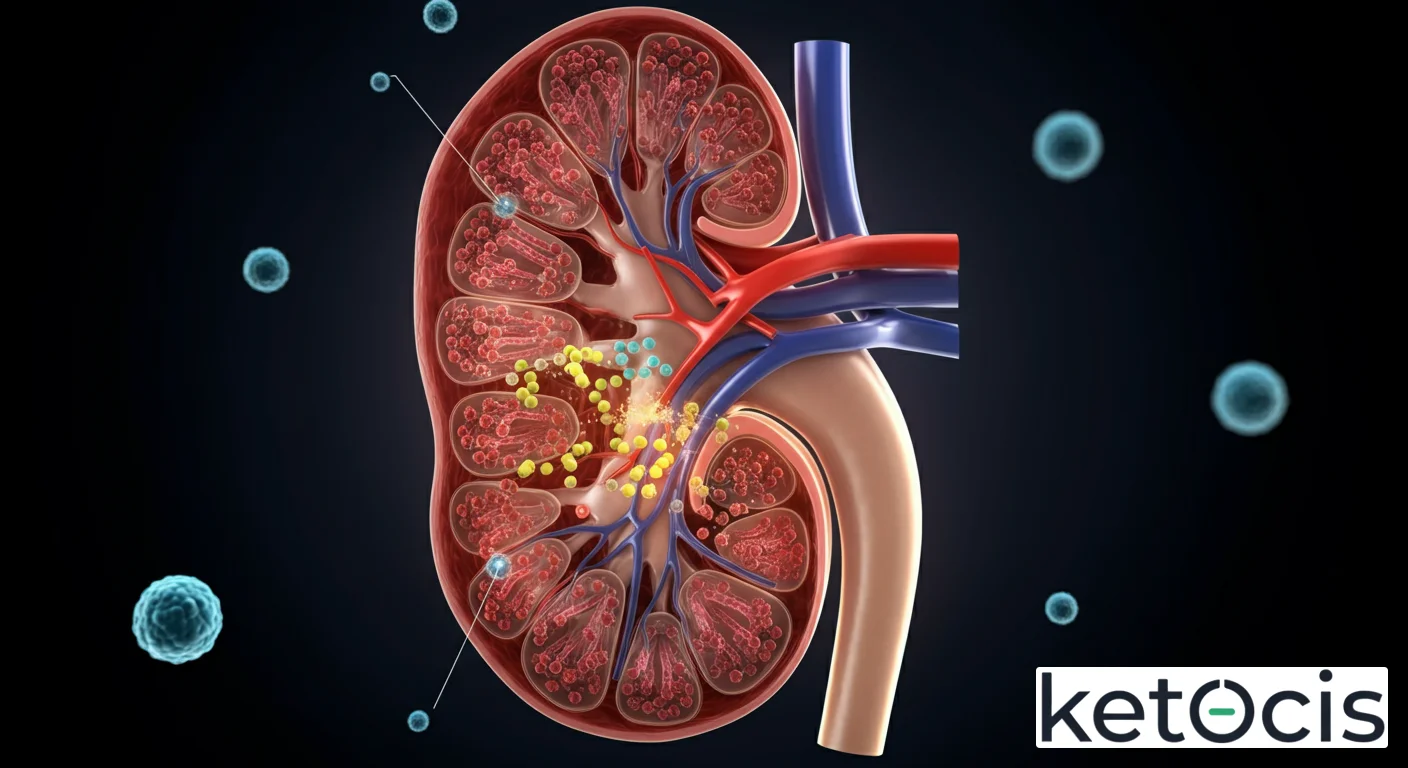

El cuerpo humano es una maravilla de ingeniería biológica, y dentro de esta intrincada red de sistemas, los riñones se erigen como los maestros de la purificación. Su función es tan vital que sin ella, la vida tal como la conocemos sería insostenible. En el corazón de esta compleja maquinaria se encuentra un proceso fundamental: el filtrado glomerular. Este no es simplemente un paso más en la formación de orina; es la primera y más crítica etapa donde la sangre se depura de toxinas, metabolitos de desecho y exceso de líquidos, manteniendo un delicado equilibrio que sustenta cada célula de nuestro organismo.

El filtrado glomerular es un proceso de filtración por presión que ocurre en el glomérulo, una red capilar especializada ubicada dentro de la cápsula de Bowman en cada nefrona. Esta maravilla microscópica es el verdadero corazón del riñón, donde la magia de la purificación comienza.

La Barrera de Filtración Glomerular

La clave de la selectividad del filtrado glomerular reside en su intrincada barrera de filtración, compuesta por tres capas principales que trabajan en conjunto para permitir el paso de agua y solutos pequeños, mientras restringen el de proteínas y células sanguíneas:

- Endotelio Capilar Fenestrado: La capa más interna está formada por células endoteliales con poros (fenestraciones) que son lo suficientemente grandes para permitir el paso de plasma, pero lo suficientemente pequeños para retener las células sanguíneas.

- Membrana Basal Glomerular (MBG): Una capa acelular compuesta por glicoproteínas y proteoglicanos con cargas negativas. Esta matriz actúa como un filtro de tamaño y carga, repeliendo proteínas cargadas negativamente, como la albúmina, que son vitales para el plasma.

- Podocitos: Células epiteliales viscerales que recubren la superficie externa de la MBG. Poseen extensiones en forma de pies (pedicelos) que se entrelazan, formando ranuras de filtración. Estas ranuras están cubiertas por diafragmas de hendidura que actúan como la última barrera de tamaño, impidiendo el paso de proteínas de tamaño medio.

La integridad de esta barrera es crucial. Daños en cualquiera de sus componentes pueden llevar a enfermedades renales, manifestándose a menudo por la presencia de proteínas (proteinuria) o sangre (hematuria) en la orina.